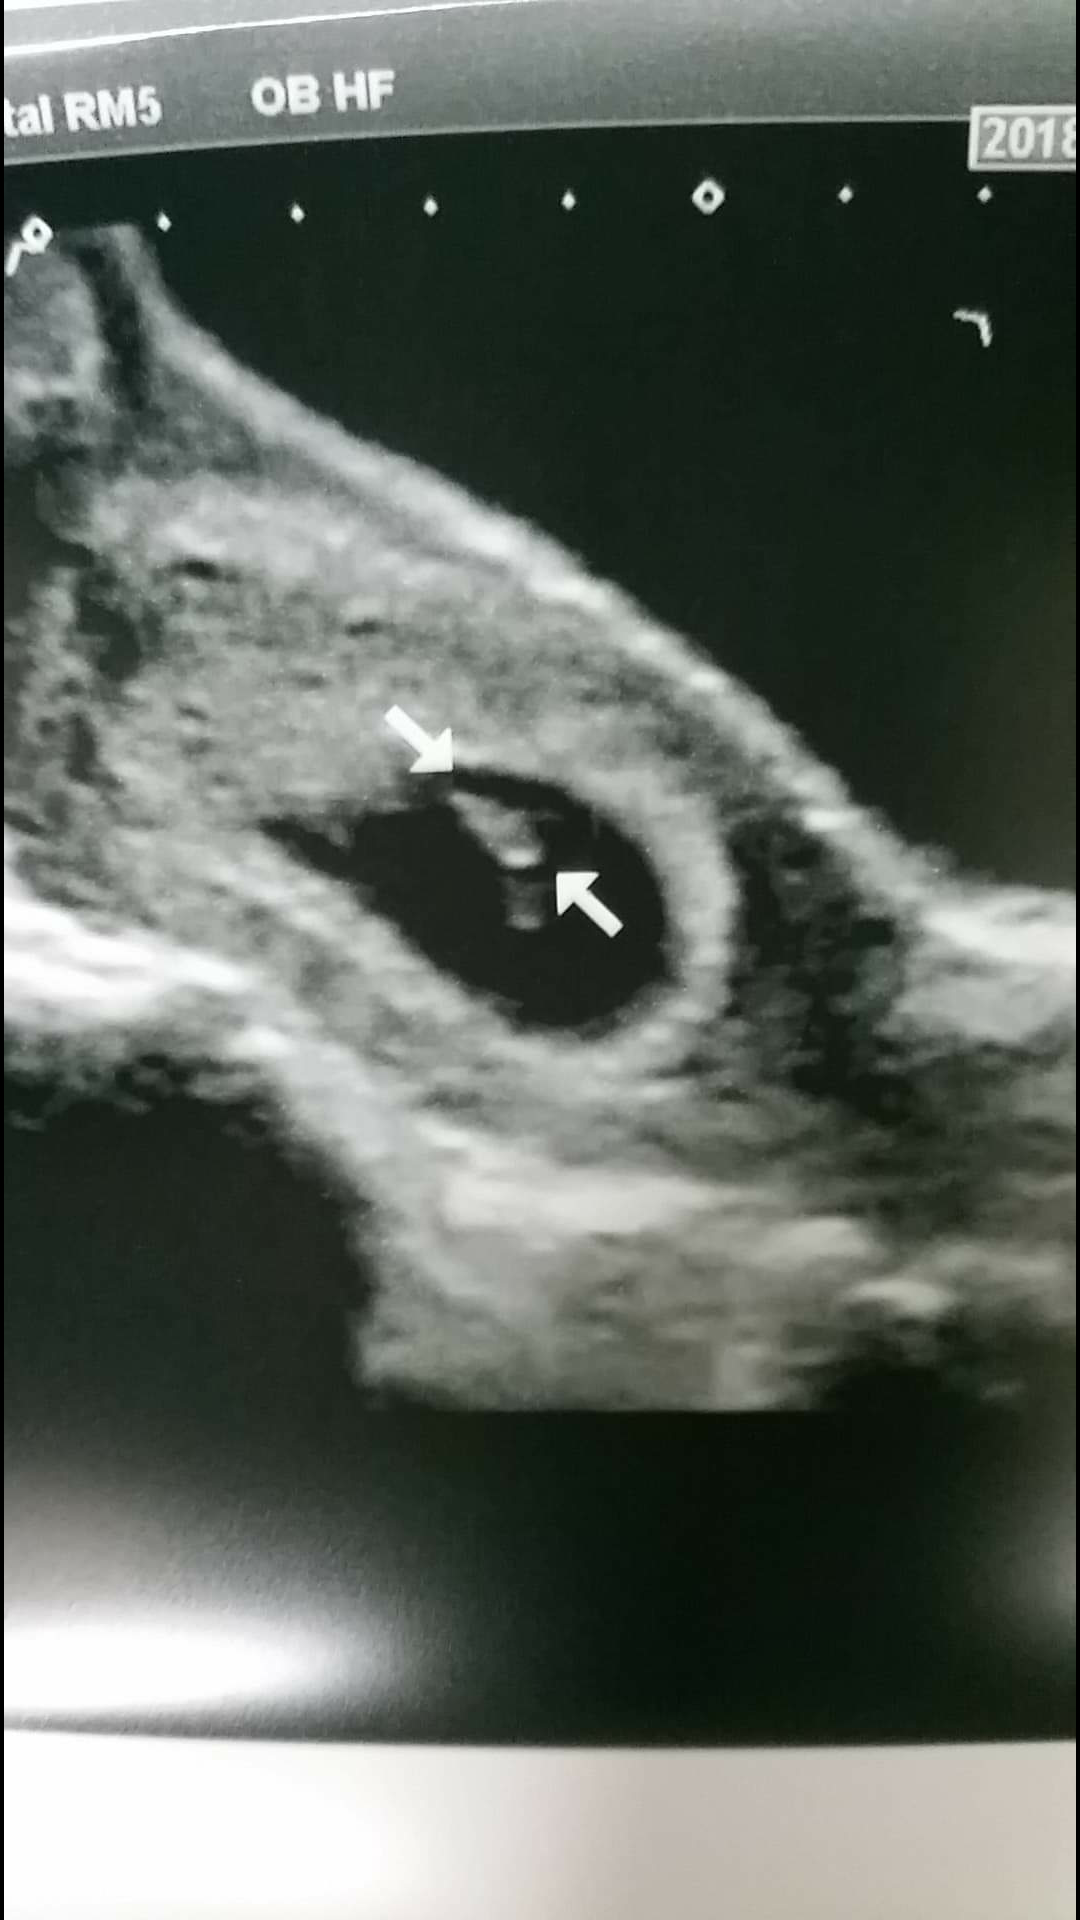

I saw the heartbeat but the tech did not share with me the heart rate or any audio.